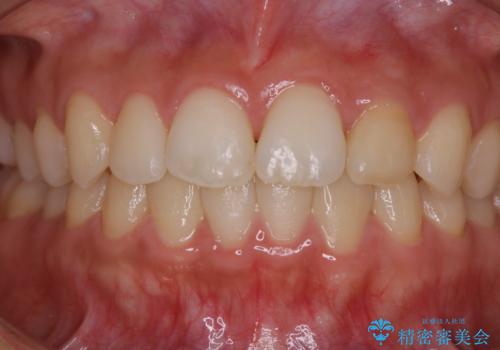

矯正治療終了後にPMTC(Professional Mechanical Tooth Cleaning)

- 矯正治療が終了したため、クリーニングでもきれいにしたいとのことでした。PMTC60分コースを行いました。

矯正治療が終わり、せっかくきれいになった歯並びも、虫歯・歯周病などになってしまっては元も子もありません。

矯正治療やセラミックなどによる被せ物の治療終了のタイミングではクリーニングを行い、汚れや着色の除去、歯と歯の間・歯と歯肉との境目などのケアをしっかりすることをおすすめしています。